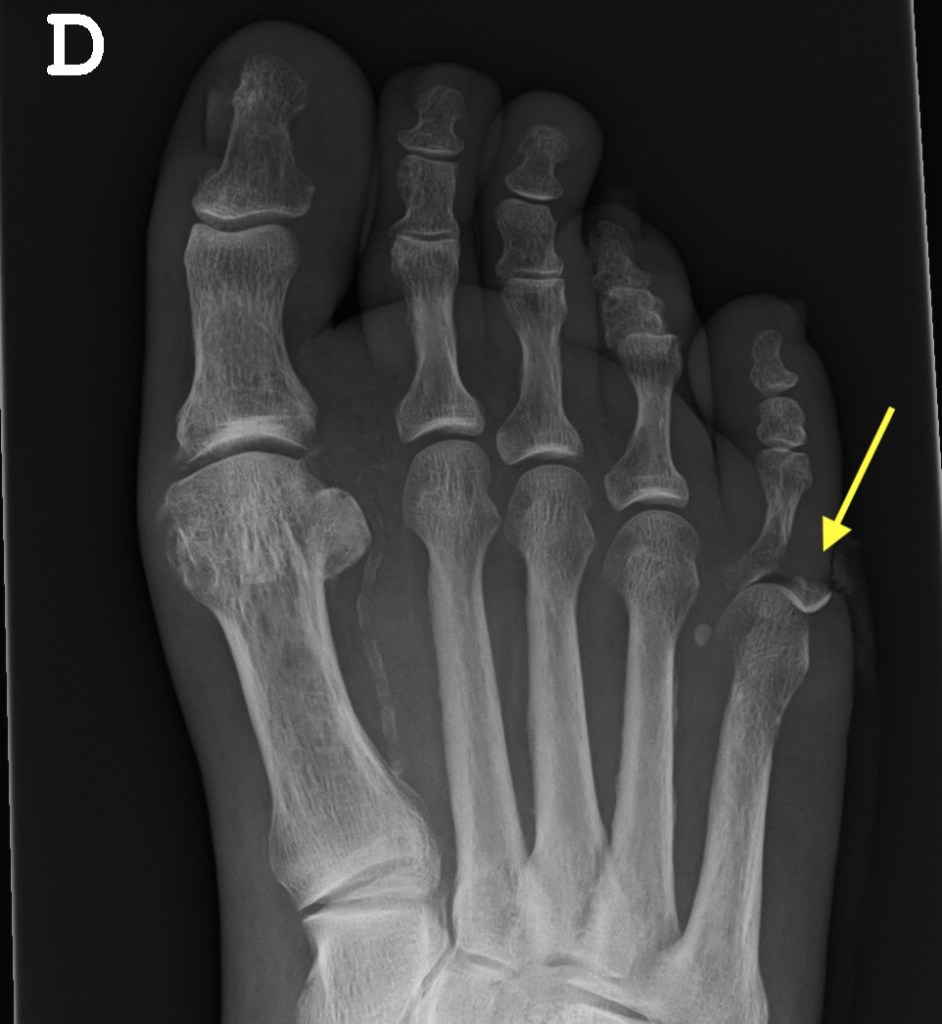

En los casos con infección es necesario realizar una radiografía en dos proyecciones del pie.

En la radiografía se puede apreciar que existe una destrucción del hueso, de la quinta articulación metatarso-falángica (flecha amarilla)